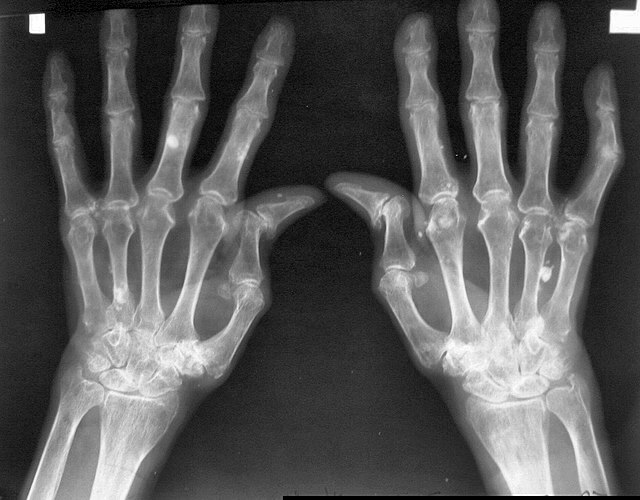

관절 X선 소견의 이상